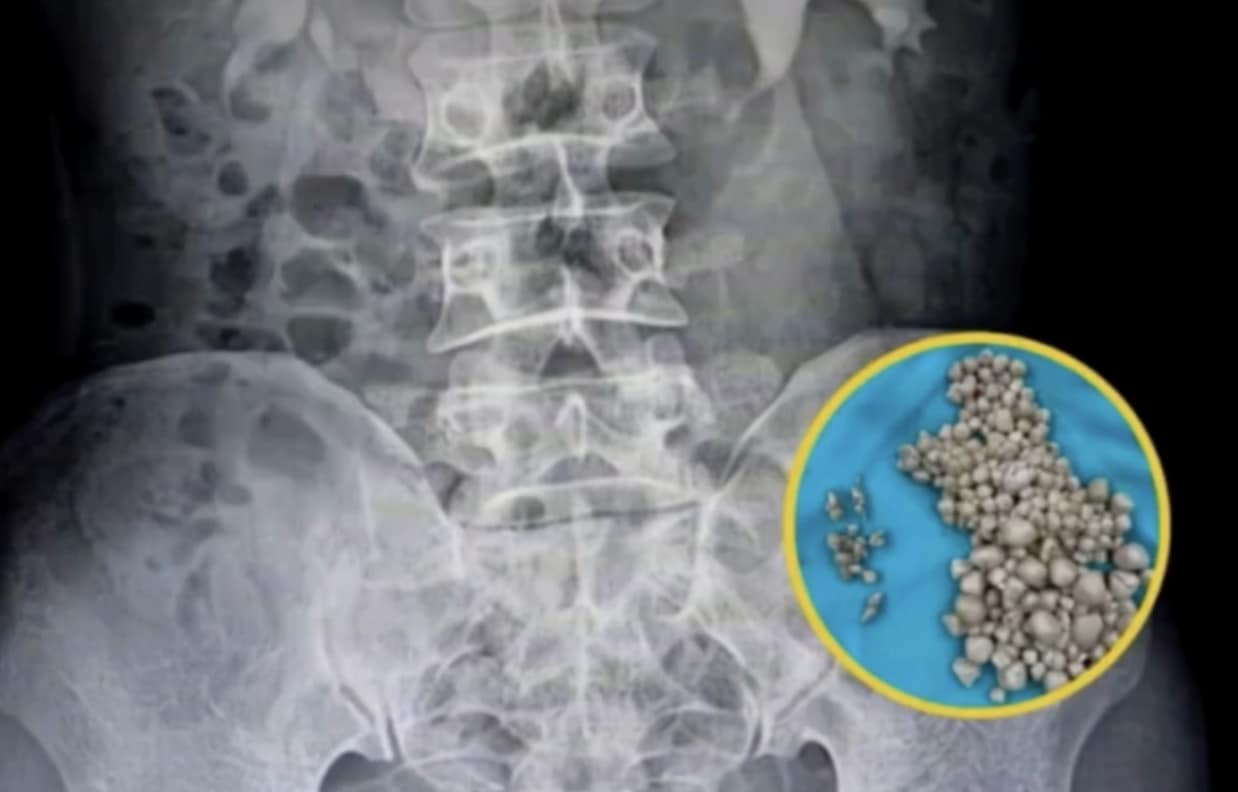

Οι χειρουργοί του νοσοκομείου πραγματοποίησαν περκοτανοσκοπική νεφρολιθοτομή, μια ελάχιστα επεμβατική διαδικασία μέσω μικρής τομής στην πλάτη. Σε διάρκεια περίπου δύο ωρών, αφαίρεσαν περισσότερους από 300 πέτρες γεμίζοντας πολλούς ιατρικούς δίσκους.

Oι πέτρες που αφαιρέθηκαν από τα νεφρά της νεαρής κοπέλας

d7385546

H ακτινογραφία με τις πέτρες πάνω αριστερά

Χωρίς την επέμβαση, η νεαρή κοιπέλα θα μπορούσε να είχε υποστεί σήψη, νεφρική ανεπάρκεια ή ακόμη και θάνατο. Η περίπτωσή της αποδεικνύει πόσο ανθεκτικό —αλλά και πόσο ευάλωτο— μπορεί να είναι το ανθρώπινο σώμα απέναντι στις καθημερινές κακές συνήθειες.